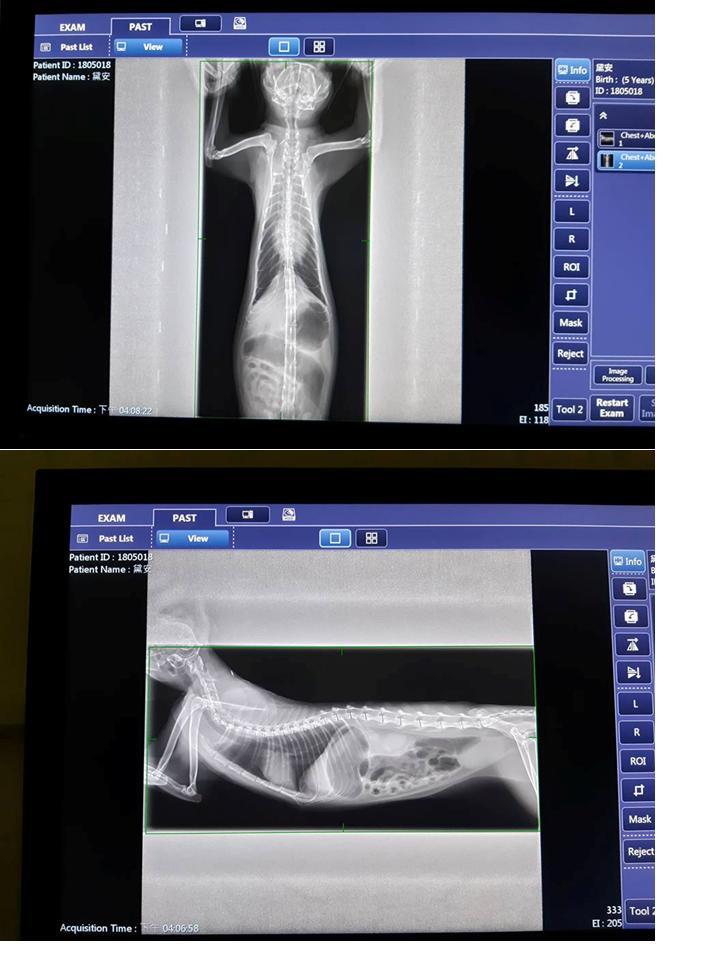

在今年5/18,照護員發現黛安有流鼻水、淚眼、無食慾等情況,於是在5/22將她接至台北澄諾醫院接受醫療,醫師為黛安進行血球及血液生化套組檢查、胰臟炎檢測、照X光,診斷黛安是上呼吸道感染,血檢顯示白血球過高,須住院施打靜脈注射、氣霧、為期五週的抗生素治療,並有進行耳疥治療。

4 左上顎第四前臼齒牙周病,牙齒搖動,建議可考慮進行牙周治療。

因黛安最近吃得不好,今天作了血檢(正常),量血壓(130),檢查口腔及耳朵(正常),也聽了心音(正常),醫生認為黛安左上方牙齒動搖應該是造成她食慾不好的原因,建議於本周四進行牙周處理。這次的藥物有加入食慾促進劑,請照護員再觀察食慾有沒有變好。

另黛安右眼會有淚水,照光檢查後發現角膜上有白斑,但無法確定是舊傷的痂痕或是進行中的傷口,建議轉眼睛專科確診。

今日拔牙、洗牙。

前次回診時,照護員有告知醫師,近日黛安食慾不好,體重下降,醫師為黛安做口腔檢查,血檢各方面都ok,找不出不吃的原因,但因黛安右上方有顆牙鬆動,醫生想處理掉那顆搖動的牙齒,因為那個位置只要咬東西就會碰到,於是今日安排拔牙洗牙,晚上6:40分接回。